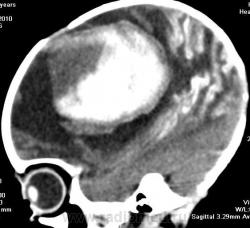

Я думаю, это больше похоже на кровоизлияние - неоднородная структура с гиперденсным компонентом. Плюс ко всему - клиника, судя по всему, с острым началом. Опухоли быстро не растут.

Смущает то, что кровоизлияние как бы в капсуле. А что с извилинами? Пропитывание кровью?

Паразитарная киста - это эхинококк? Образование имеет плотность свежей крови, так что кровоизлияние не вызывает сомнений. Но вот возможно кровоизлияние в опухоль или в результате какой-либо сосудистой патологии, например, ангиоматоза Штурге-Вебера. Насчет течения родов попробую уточнить.

Светлые участки 70 ед Н - плотности крови.

А ведь кровоизлияние есть субарохноидально.

Денди Уокер? Не думаю, хотя надо посмотреть аксиалы ниже уровня намёта. А пока явно вижу признаки Sturge-Weber syndrome - encephalotrigeminal angiomatosis синдром со всеми вытекающими.